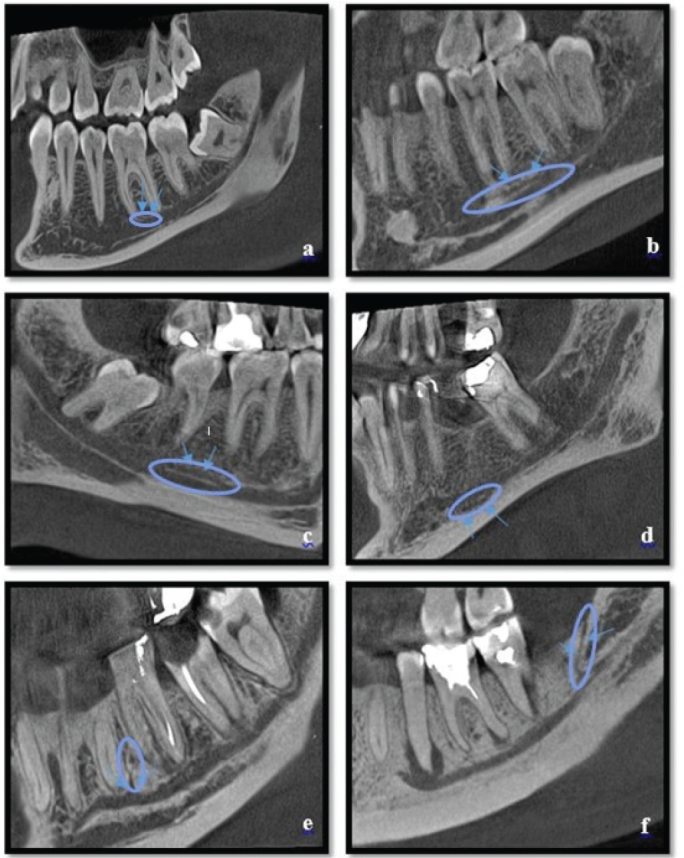

Methods: Cone-beam computed tomography (CBCT) images were evaluated. AMC's frequency, length, and diameter, including dental, superior, inferior, forward-open, forward-closed, and retromolar types, were determined. Additionally, the dimensions of the MC, including its length and diameter, were measured, and the relationship between the AMC and MC was statistically analyzed. Descriptive statistics, chi-square test, independent samples t-test (for normally distributed data), Kruskal-Wallis test (for non-normally distributed data), and Tamhane post hoc test were used for statistical analysis of the data.

Results: AMC was identified in 82 of the 222 hemimandibles examined (36.9%). It was found that the length and diameter of AMCs varied significantly depending on the AMC type (p = 0.000). The diameter of the dental type AMCs (mean 0.40 ± 0.22 mm) was considerably smaller than that of other AMC types (mean 0.86 ± 0.37 mm). The length and diameter of the MC were measured as 69.20 ± 5.10 mm and 2.96 ± 0.57 mm, respectively. While MC length was not found to influence the presence of AMC (p = 0.785), MC diameter was significantly associated with the occurrence of AMC (p = 0.000).